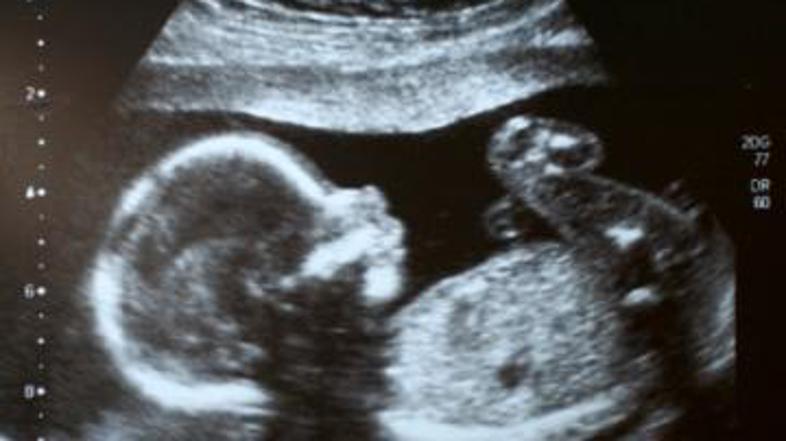

ultrazvok Žurnal24 main

Postojnska porodnišnica bo morala družini iz Nove Gorice plačati 800.000 evrov odškodnine zaradi zapletov pri porodu, pri katerem je novorojenček dobil trajne poškodbe možganov, poročajo Primorske novice.